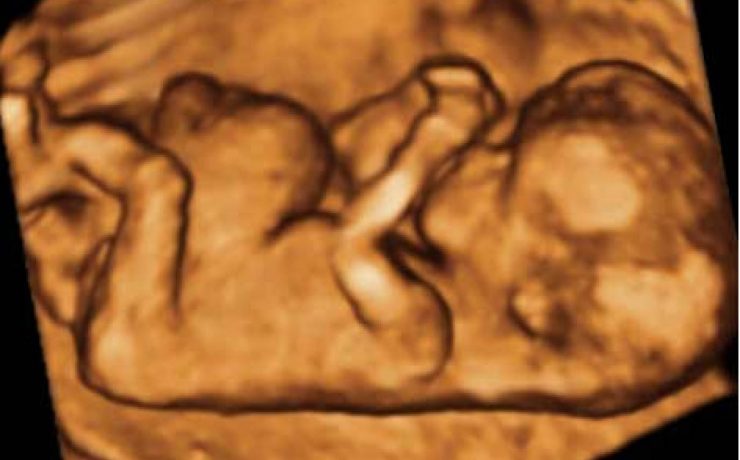

La apendicitis aguda durante el embarazo constituye la causa más frecuente de abdomen agudo quirúrgico no obstétrico, reportándose a nivel mundial una incidencia de 0.1 a 1.4 casos por cada 1,000 embarazadas. Algunos estudios en América Latina han reportado una incidencia aproximada de 1 por cada 1,200 embarazos. El diagnóstico